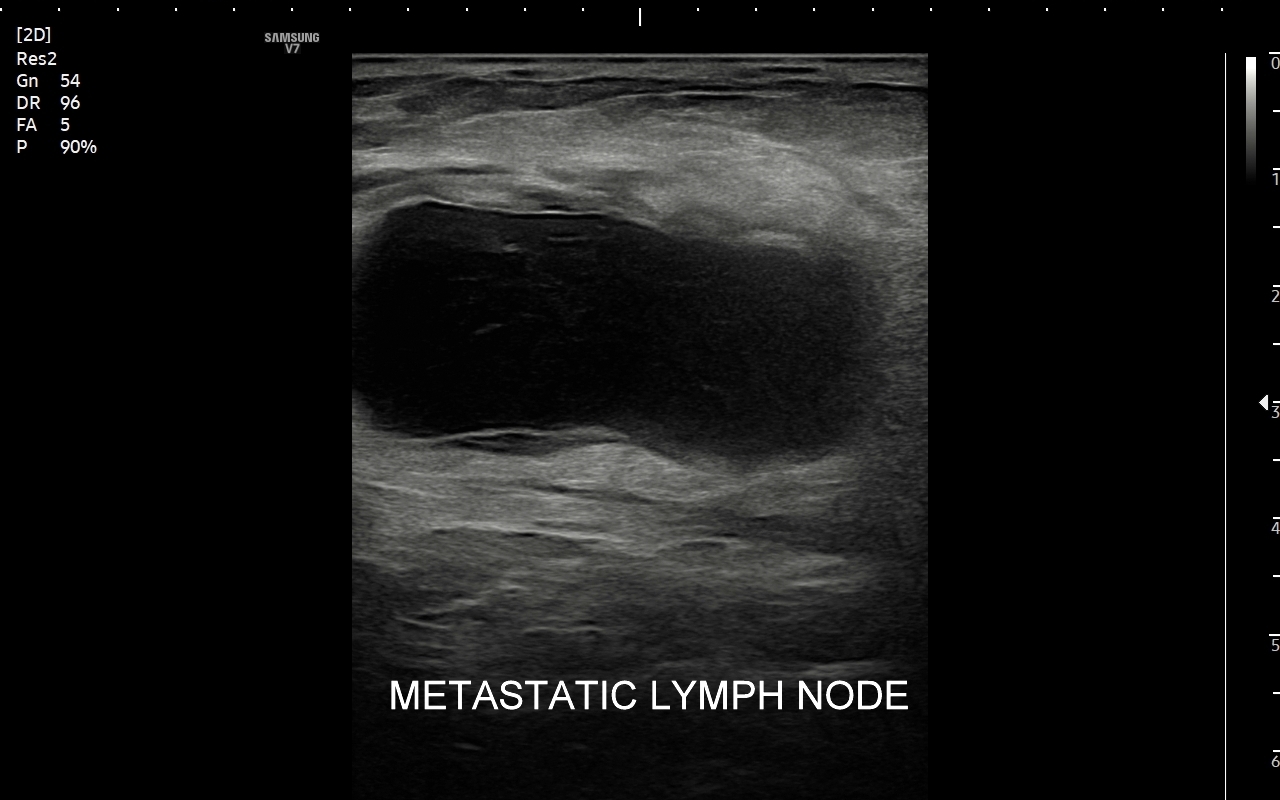

W przebiegu chorób, w których dochodzi do stymulacji układu odpornościowego, węzły limfatyczne ulegają powiększeniu. Przykładami są miejscowe lub uogólnione procesy zapalne i autoimmunologiczne, schorzenia infekcyjne bakteryjne, wirusowe, grzybicze i pasożytnicze. Węzły chłonne powiększać się mogą również w przebiegu białaczek i chłoniaków, a także w trakcie chorób nowotworowych, w których dochodzi do tworzenia przerzutów.

Badanie USG jest podstawową metodą obrazowania węzłów chłonnych. W jego trakcie ocenia się nie tylko wielkość węzłów, lecz także ich kształt, proporcje wymiarów, morfologię, czyli wygląd zewnętrzny oraz strukturę wewnętrzną, ich unaczynienie, spoistość, a także tkanki otoczające. W trakcie interpretacji badania pod uwagę bierze się również zbierany od pacjenta wywiad chorobowy oraz wyniki innych badań obrazowych i laboratoryjnych takich jak morfologia, OB, CRP, żelazo, ferrytyna, TIBC, innych parametrów infekcyjnych, a także onkologicznych. Ultrasonografia węzłów chłonnych jest procedurą bezpieczną i dokładną. W Pracowni dr Szczepańskiego węzły chłonne oceniane są nowoczesną metodą MPUS (multiparametryczne badanie USG), w szczególności z zastosowaniem trybów mikrounaczynienia i elastografii.

Do powiększenia węzłów chłonnych szyi, stanu określanego jako limfadenopatia, dochodzi najczęściej w przebiegu chorób zakaźnych górnych dróg oddechowych, wirusowych i bakteryjnych. Inne przykłady przyczyn limfadenopatii szyjnej obejmują ropne choroby zębów, migdałków i zatok przynosowych; odczyny w chorobach autoimmunologicznych, np. w chorobie Hashimoto i Sjögrena; a także rozrostowe schorzenia układu hematologicznego (białaczki i chłoniaki) i choroby nowotworowe jak np. rak tarczycy, krtani, migdałka, czy języka. Należy mieć na uwadze, iż w przypadku podejrzenia chorób układu krwiotwórczego oraz mononukleozy zakaźnej, oprócz węzłów chłonnych, niezbędne jest również badanie USG wątroby i śledziony. W części przypadków, gdy podejrzewa się możliwość choroby nowotworowej lub w celu jej wykluczenia, lekarz może zalecić rozszerzenie diagnostyki obrazowej na inne obszary ciała.